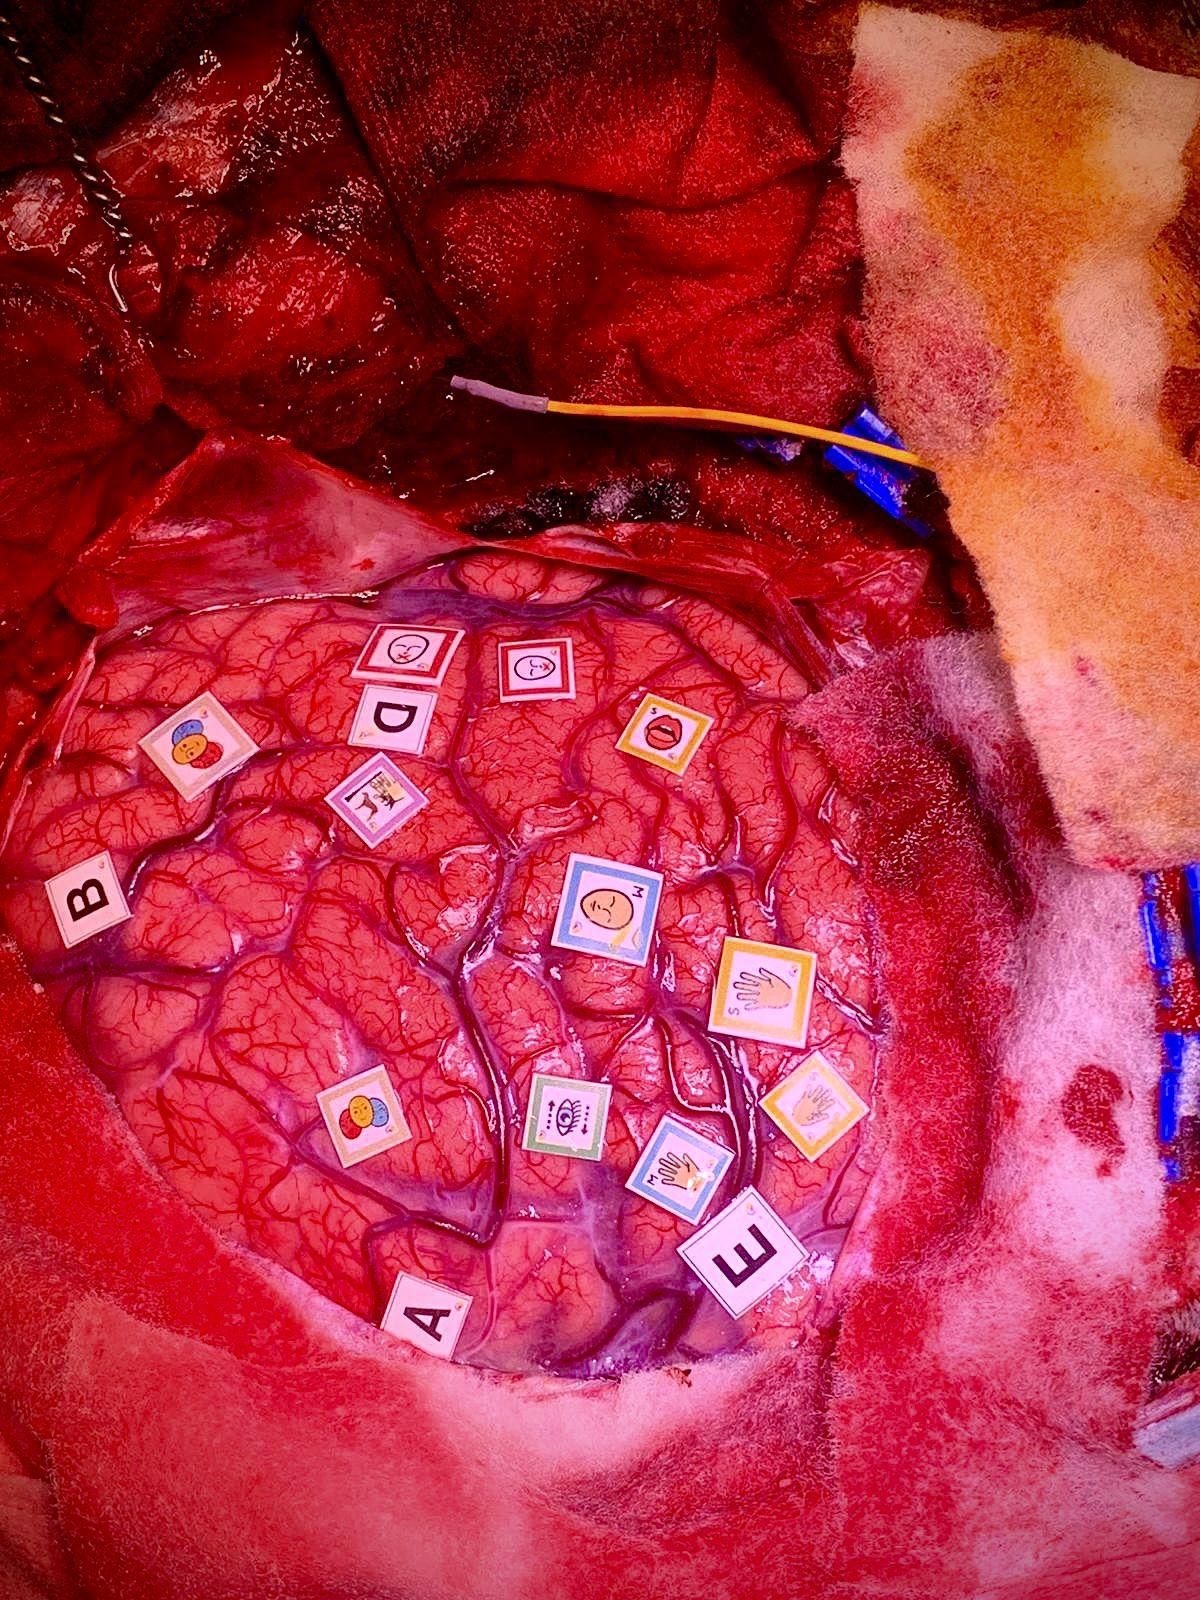

El neurocirujano palmero Jesús Martín-Fernández durante la intervención.

El joven neurocientífico, neurocirujano y compositor palmero Jesús Martín-Fernández, de 30 años, que actualmente trabaja en Francia con su mentor Hugues Duffau, hizo el pasado miércoles historia en el Hospital del Mar de Barcelona al llevar a cabo, junto a su equipo, la primera cirugía despierta en España de un tumor cerebral localizado en el hemisferio derecho, consiguiendo identificar y respetar áreas encargadas de la personalidad, las emociones y la cognición social. Además, aplicó, por primera vez en el mundo, un test de inteligencia artificial con metahumanos (avatares), diseñado por él, durante la cirugía, con el paciente despierto, para identificar qué partes del cerebro del paciente se encargan de procesar las emociones, según información facilitada a este periódico.

El cerebro de la paciente durante la intervención.

La paciente, con un tumor cerebral (llamado glioma de bajo grado) realizó durante toda la intervención determinadas tareas específicas para evaluar constantemente funciones cognitivas tan complejas como la atención, la memoria a corto plazo, la cognición social, consiguiendo así extirpar el tumor en zonas que históricamente han sido consideradas como “no extirpables” o vitales para estas funciones. Bajo esta técnica, y con ayuda de este sistema de metahumanos con emociones en movimiento creado por el Dr. Jesús Martín y el diseñador de inteligencia artificial 3D Fran Pérez, la paciente se encuentra sin déficits cognitivos tras la compleja cirugía a la que ha sido sometida.